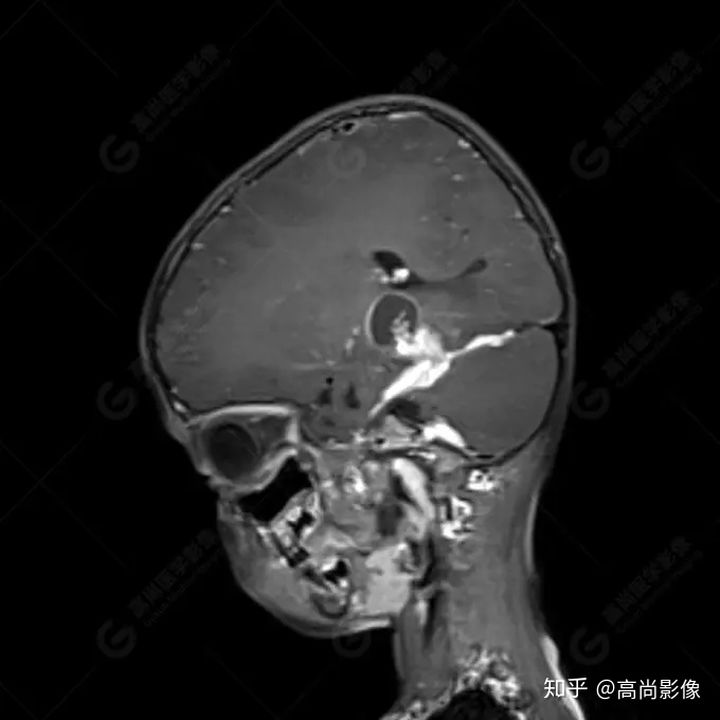

右側(cè)顳葉腫瘤切除術(shù)后(具體不詳):右側(cè)顳部骨質(zhì)不連續(xù)呈術(shù)后改變,右側(cè)顳葉術(shù)區(qū)見片狀長T1長T2信號(hào)影,F(xiàn)LAIR呈低信號(hào);術(shù)區(qū)后方右側(cè)顳枕葉見一巨大占位性病變影,邊界欠清,大小約6.2×5.8×4.3cm(前后×左右×上下),信號(hào)不均勻,T1WI呈等稍低信號(hào)間雜少許高信號(hào),T2WI呈高稍低混雜信號(hào),DWI示部分病灶彌散受限,相應(yīng)ADC圖減低,磁敏感序列見部分呈極低信號(hào),增強(qiáng)掃描可見明顯不均勻強(qiáng)化,鄰近硬腦膜及小腦幕增厚并明顯強(qiáng)化;另延髓右前方及右側(cè)橋小腦角區(qū)見一不規(guī)則形異常信號(hào)影,大小約3.2×1.3×3.7cm(左右×前后×上下),呈長T1稍長T2信號(hào),F(xiàn)LAIR呈等信號(hào),DWI未見受限,增強(qiáng)后明顯均勻強(qiáng)化,鄰近腦膜明顯強(qiáng)化。鄰近腦實(shí)質(zhì)及右側(cè)顳角明顯受壓;左側(cè)大腦半球未見局灶性信號(hào)異常,中線結(jié)構(gòu)稍左移。

MR診斷

右側(cè)顳葉腫瘤切除術(shù)后:現(xiàn)術(shù)區(qū)后方右側(cè)顳枕葉及延髓右前方占位,右側(cè)顳枕部硬腦膜及小腦幕明顯強(qiáng)化,結(jié)合既往影像資料,考慮為胚胎源性惡性腫瘤,如非典型畸胎樣/橫紋肌樣瘤(AT/RT)或原始神經(jīng)外胚層腫瘤(PNET)。